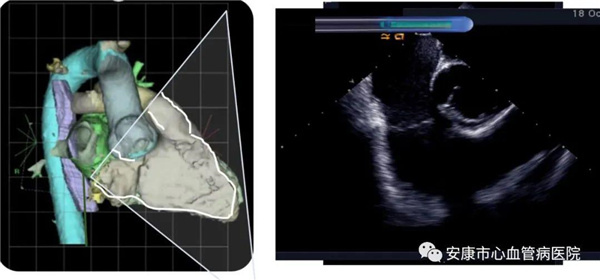

心律失常團隊在11月6日為患者在ICE引導(dǎo)下行房撲射頻消融術(shù)。穿刺左鎖骨下靜脈,導(dǎo)絲走行證實了合并永存左上腔靜脈。穿刺右股靜脈,分別送入心腔內(nèi)超聲導(dǎo)管和消融電極,超聲下建立右心室、右心房、左心室、左心房、二尖瓣和三尖瓣及三尖瓣峽部模型。ICE就像術(shù)者多了一雙天眼,可以對心臟內(nèi)部結(jié)構(gòu)一目了然,360度無死角觀察心臟結(jié)構(gòu),可以做到“所視即所及”。建模后,消融三尖部峽部,房撲很快終止,轉(zhuǎn)為竇性心律,手術(shù)獲得成功!手術(shù)用時僅70分鐘,術(shù)后病情穩(wěn)定,安全返回病房。

心腔內(nèi)超聲(Intracardiac Echocaiography ICE)是將微型的換能器安裝在心導(dǎo)管的尖端,再經(jīng)外周血管(動脈或靜脈)送至心腔,換能器發(fā)射聲波,然后將接受到的回波經(jīng)計算機處理后形成超聲圖像。由于換能器放置在心腔內(nèi),不受空氣等因素的干擾,因此比經(jīng)食道超聲檢查圖像更加清晰,可以辨別心內(nèi)的細微結(jié)構(gòu),臨床上主要用于指導(dǎo)心律失常的射頻消融治療。

ICE不僅能檢查左心耳結(jié)構(gòu)、指導(dǎo)房間隔穿刺,而且能精確構(gòu)建左房及肺靜脈解剖結(jié)構(gòu),量化前庭部位與肺靜脈口部的距離,精準的消融一些復(fù)雜心律失常病例;并且能精確構(gòu)建食道,量化食道與后壁的距離,降低食道損傷幾率;術(shù)中動態(tài)監(jiān)測積液變化,實時監(jiān)測并發(fā)癥,早發(fā)現(xiàn)早處理。因此心腔內(nèi)超聲真可謂是房顫射頻消融手術(shù)安全保障的一只“天眼”。此外這只“天眼”現(xiàn)在還應(yīng)用于心臟瓣膜手術(shù)、起搏器植入等心臟介入手術(shù)。